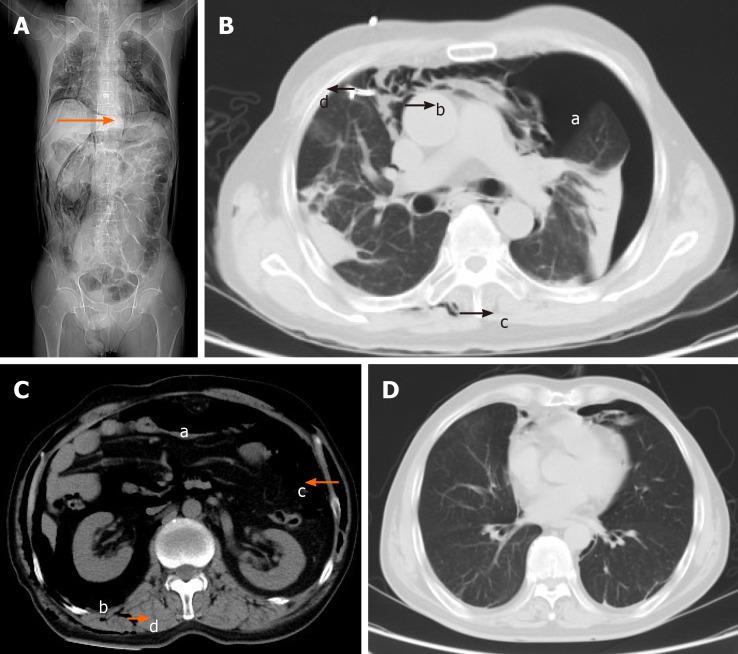

Herein, we describe a patient with intestinal BD who presented with decreased oxygen saturation and shortness of breath during a diagnostic colonoscopy. Bilateral pneumothorax, pneumomediastinum, pneumoperitoneum, pneumoretroperitoneum and subcutaneous emphysema of the neck, chest, abdomen, back and scrotum were confirmed by computed tomography scan. The sudden change in condition was considered to be associated with iatrogenic bowel perforation. After receiving closed thoracic drainage and conservative therapy, the patient was discharged in stable condition.

在此,我们描述一名肠道BD患者,其在诊断性结肠镜检查期间出现氧饱和度下降和呼吸急促。计算机断层扫描证实存在双侧气胸、纵隔气肿、气腹、腹膜后气肿以及颈部、胸部、腹部、背部和阴囊的皮下气肿。病情的突然变化被认为与医源性肠穿孔有关。在接受闭式胸腔引流和保守治疗后,患者病情稳定出院。